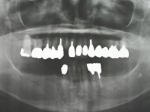

術前レントゲン